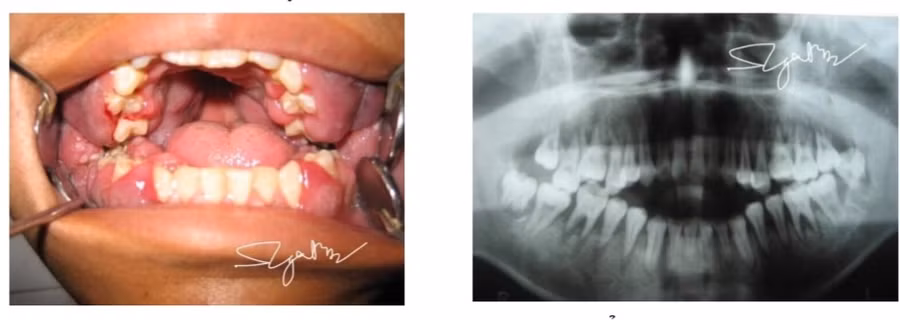

Các bác sĩ chẩn đoán bệnh nhân mắc leucemie cấp (ung thư máu cấp tính). Ảnh: BVCC

Mới đây, Khoa Răng - Hàm - Mặt, Bệnh viện Bạch Mai tiếp nhận một bệnh nhân nam 16 tuổi, được chuyển tuyến từ một bệnh viện ở miền Trung với chẩn đoán viêm lợi tối cấp hoại tử.

Trước đó, bệnh nhân hoàn toàn khỏe mạnh, chưa từng mắc một bệnh nội khoa nào khác. Gần đây, bệnh nhân đột ngột khởi phát sưng lợi toàn bộ 2 hàm. Tổn thương tiến triển nhanh, người mệt mỏi, kèm theo sốt nhẹ 38 độ C. Bệnh nhân được nhập viện tỉnh điều trị. Song, sau 5 ngày, bệnh tình càng trầm trọng nên đã chuyển tuyến Trung ương.

Tại Bệnh viện Bạch Mai, bệnh nhân mệt mỏi, da xanh, niêm mạc nhợt, sốt 38,5 độ C, miệng ngậm không kín, chỉ có 2 răng hàm chạm nhau. Lợi 2 hàm thâm nhiễm cực nặng, răng toàn bộ 2 hàm lung lay độ 2, 3.

Ngay lập tức, bệnh nhân được xét nghiệm công thức máu cấp. Sau khi mời hội chẩn chuyên gia huyết học, bằng các xét nghiệm chuyên sâu, các bác sĩ chẩn đoán bệnh nhân mắc leucemie cấp (ung thư máu cấp tính) và được chuyển điều trị theo đúng chuyên khoa.